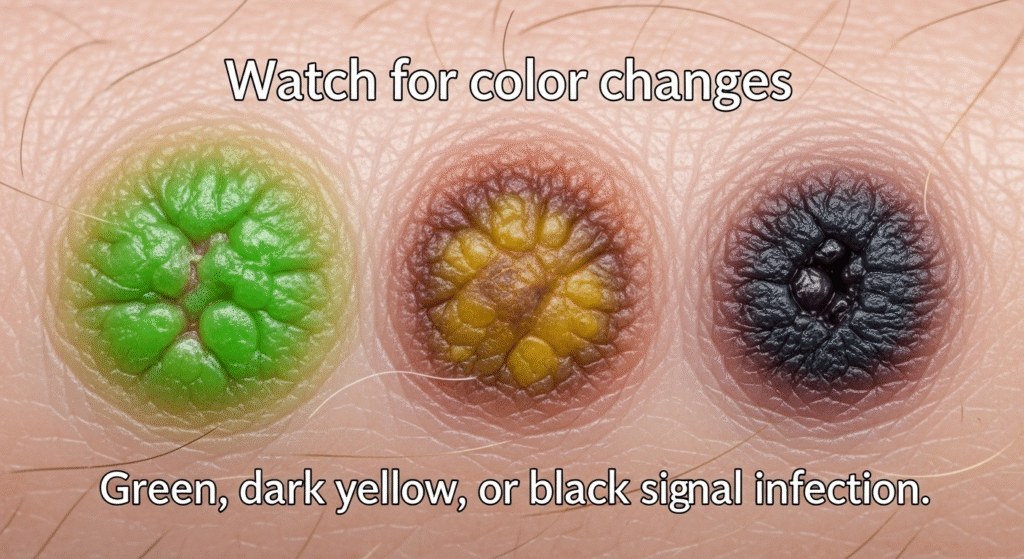

- Watch for color changes

Green, dark yellow, or black areas signal infection.